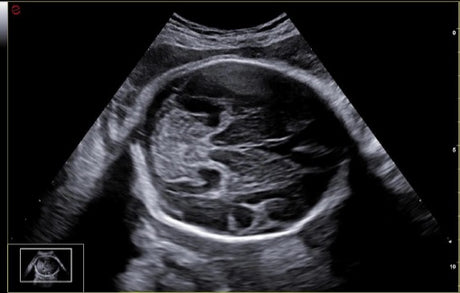

Les échographes Esaote offrent une restitution d’image d’une grande précision, permettant un diagnostic fiable dans toutes les spécialités. Le traitement numérique optimise le contraste et la netteté, réduisant les artefacts et améliorant la détection des tissus pathologiques. Ces performances sont particulièrement appréciées en gynécologie, où la lisibilité des structures pelviennes ou obstétricales est déterminante.

Un gynécologue privilégiera un échographe offrant une résolution d’image très fine et une compatibilité avec des sondes endocavitaires. Un kinésithérapeute ou un médecin du sport recherchera plutôt un appareil portable, léger et rapide à mettre en route. Les praticiens généralistes apprécieront la polyvalence et la facilité d’entretien, tandis que les vétérinaires auront besoin d’un système robuste et facilement transportable.